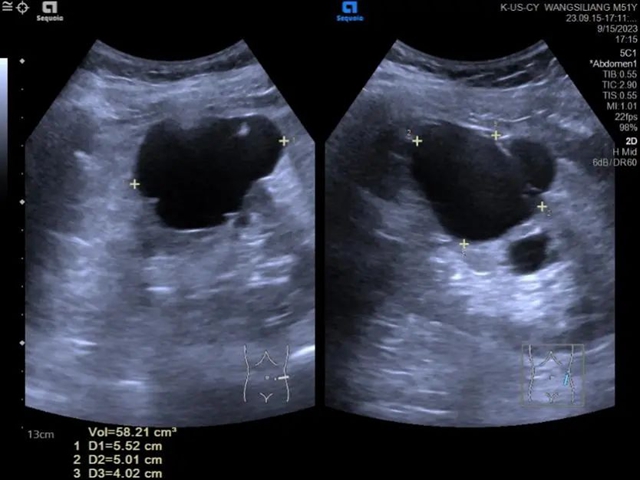

术前超声所见:

左肾中上份囊肿,大小约5.5x5.0x4.0cm(体积约58.2cm3),内见少许光带分隔。

术中超声所见:

在超声引导下置入导丝和导管后,抽取少许囊液进行蛋白试验,并经导管注入稀释后的造影剂,显示造影剂局限于囊肿内(表明囊肿与肾盂不相通)。

术后3月复查超声:

左肾囊肿较术前明显缩小,大小约1.5x1.3x1.0cm,达到治疗目的,且患者皮肤仅有针眼大小的创口。